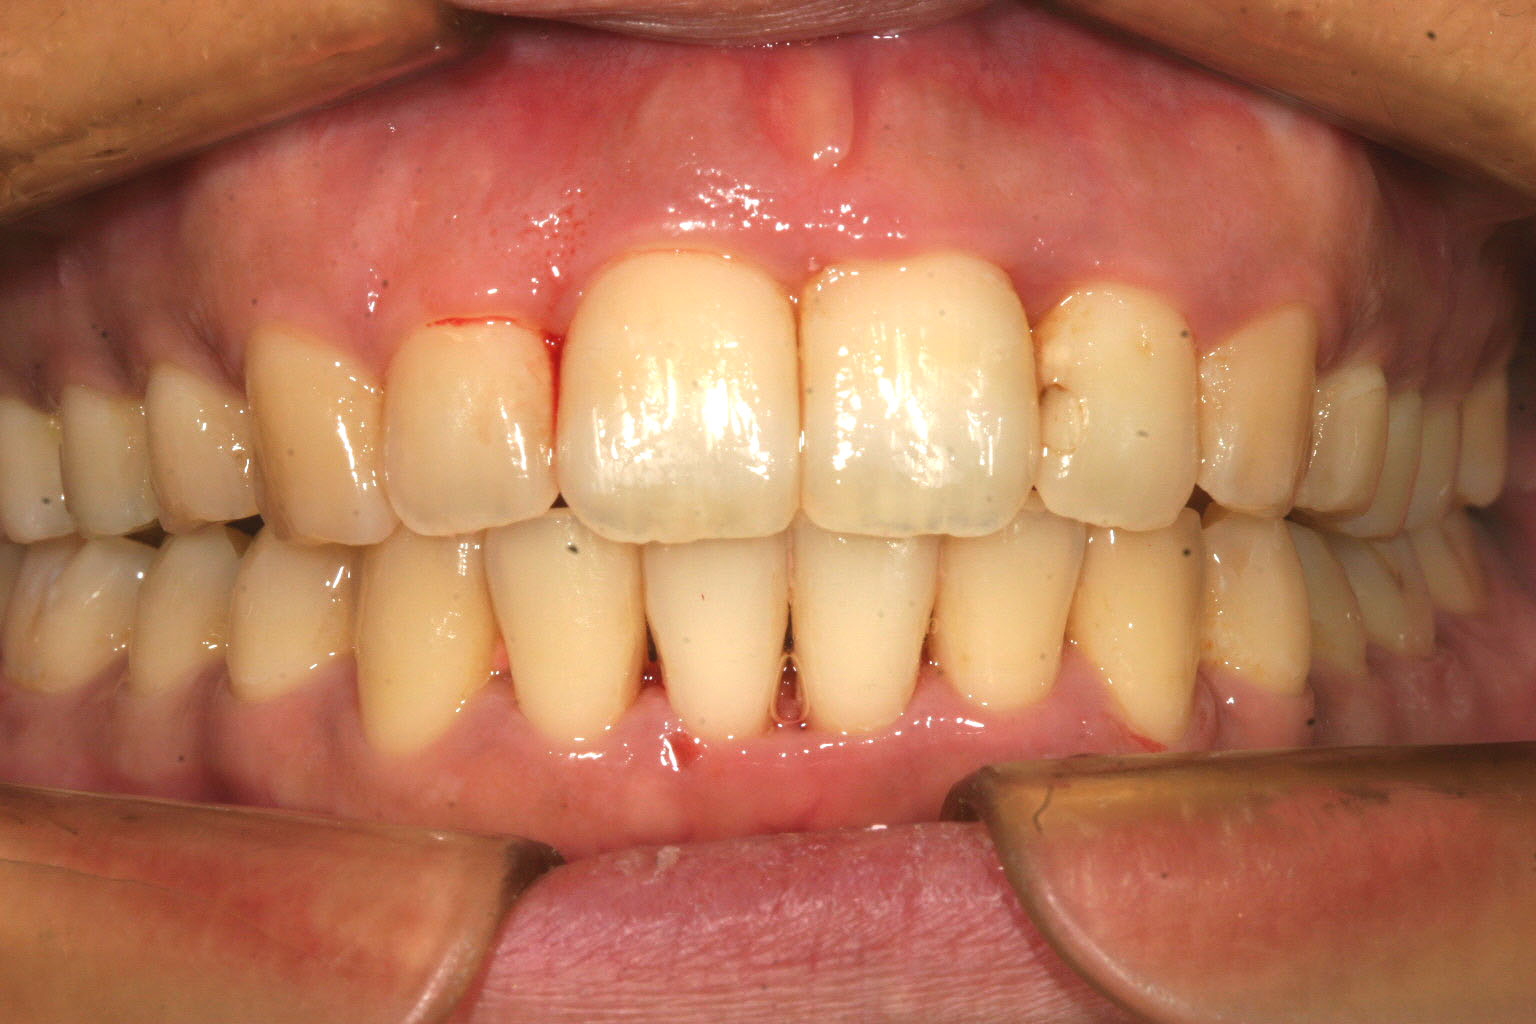

下顎も綺麗に並びました。

完全に出っ歯が改善しました。

前回の写真と比較しますと分かると思うのですが抜歯しなくてもここまでの改善が出来ます。

これはインビザラインの機能であるIPR(歯と歯の隙間を削る)と言う方法を使う事によりでっぱをここまで改善致しました。